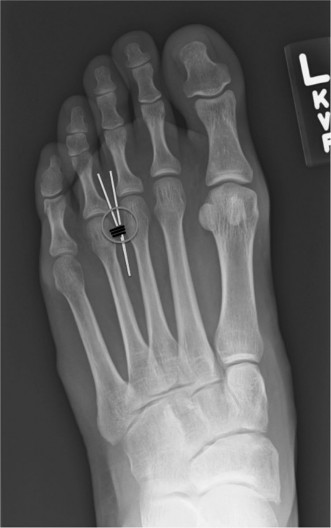

Metatarsal Osteotomy If Performed

Medial eminence resection alone does not correct the underlying metatarsus primus varus (increased IMA) or the valgus angulation of the proximal phalanx. An osteotomy is usually required to correct these angular deformities.

-

Distal Metatarsal Osteotomies (e.g., Chevron, Austin, Reverdin-Green): Used for mild to moderate deformities (IMA < 16-18°).

- A V-shaped or L-shaped cut is made in the metatarsal head or neck.

- The distal fragment (including the metatarsal head and articular surface) is translated laterally to reduce the IMA.

- Rotation can also be incorporated to address metatarsal pronation.

- Fixation is typically with a single screw, K-wire, or absorbable pin.

Figure 4: Intraoperative image demonstrating a distal metatarsal osteotomy (e.g., Chevron) with planned screw fixation. -